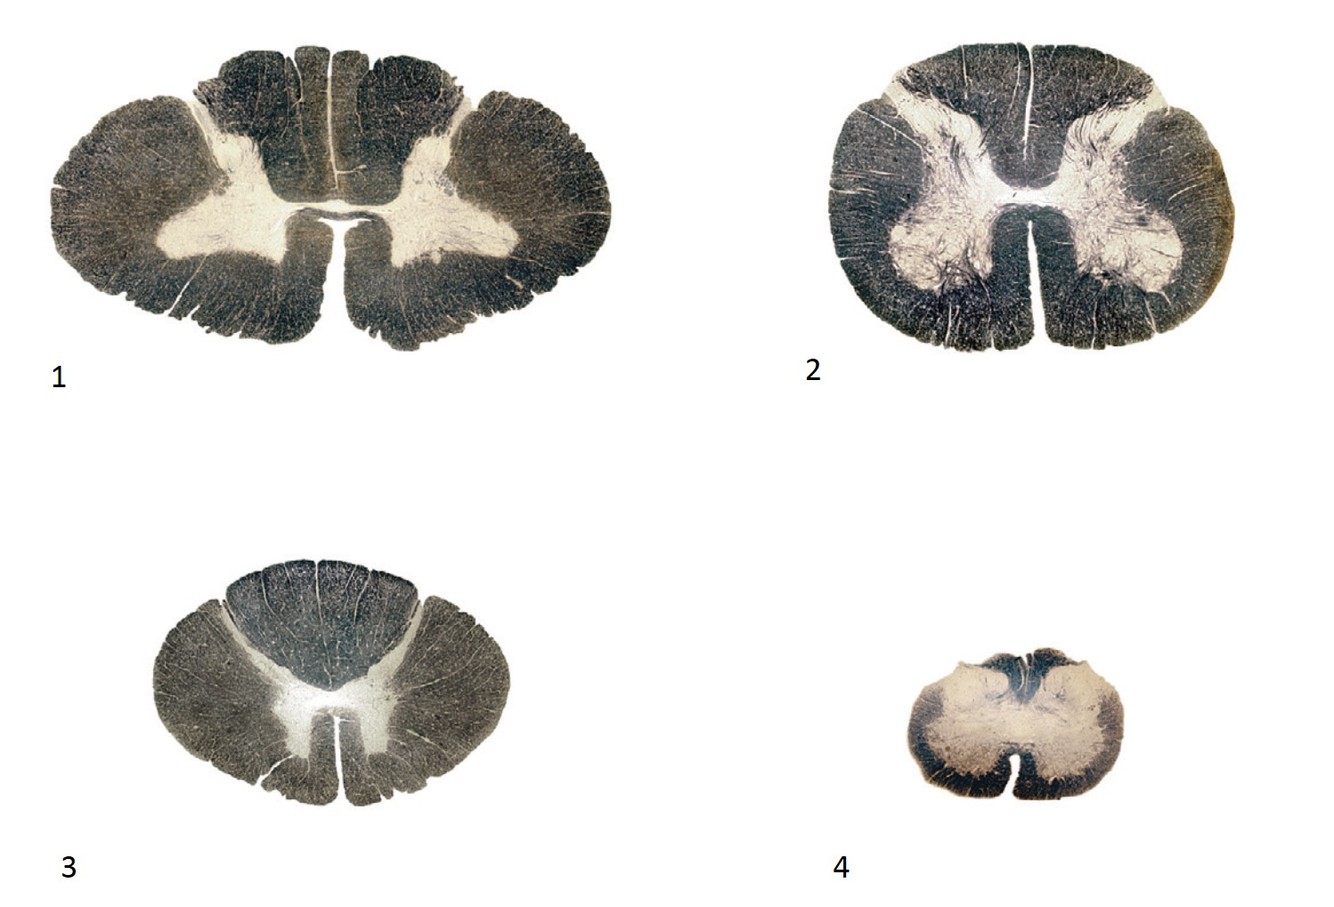

The cross section corresponds to which level of the spinal cord:

Thoracic

What is the correct order of spinal cord sections from cranial to caudal?

1, 3, 2, 4